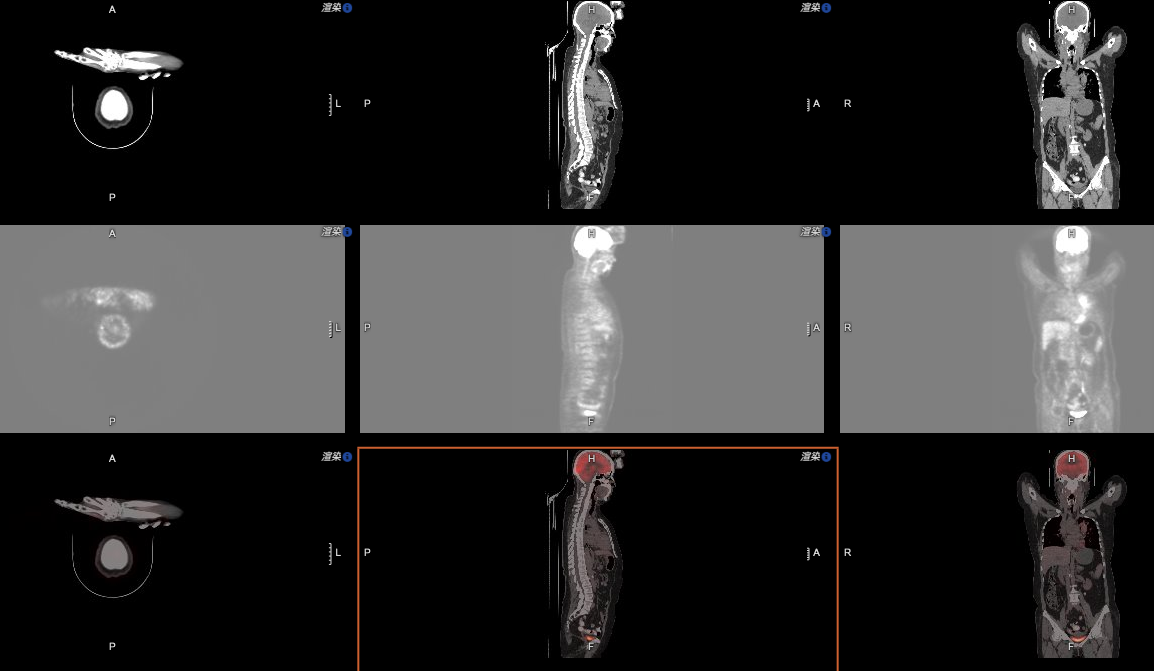

再看這張圖:

相信對(duì)于具備PET/CT的醫(yī)療機(jī)構(gòu)來說,這樣的影像軟件功能同樣是必需的。

因此,影像軟件的功能決定了影像云的適用范圍,基礎(chǔ)軟件用于DR影像的閱片沒有任何壓力,但對(duì)于高端醫(yī)療設(shè)備,如果軟件功能不足,部分設(shè)備以及部位的影像可能得不到針對(duì)性的后處理,診斷的價(jià)值隨之受損。